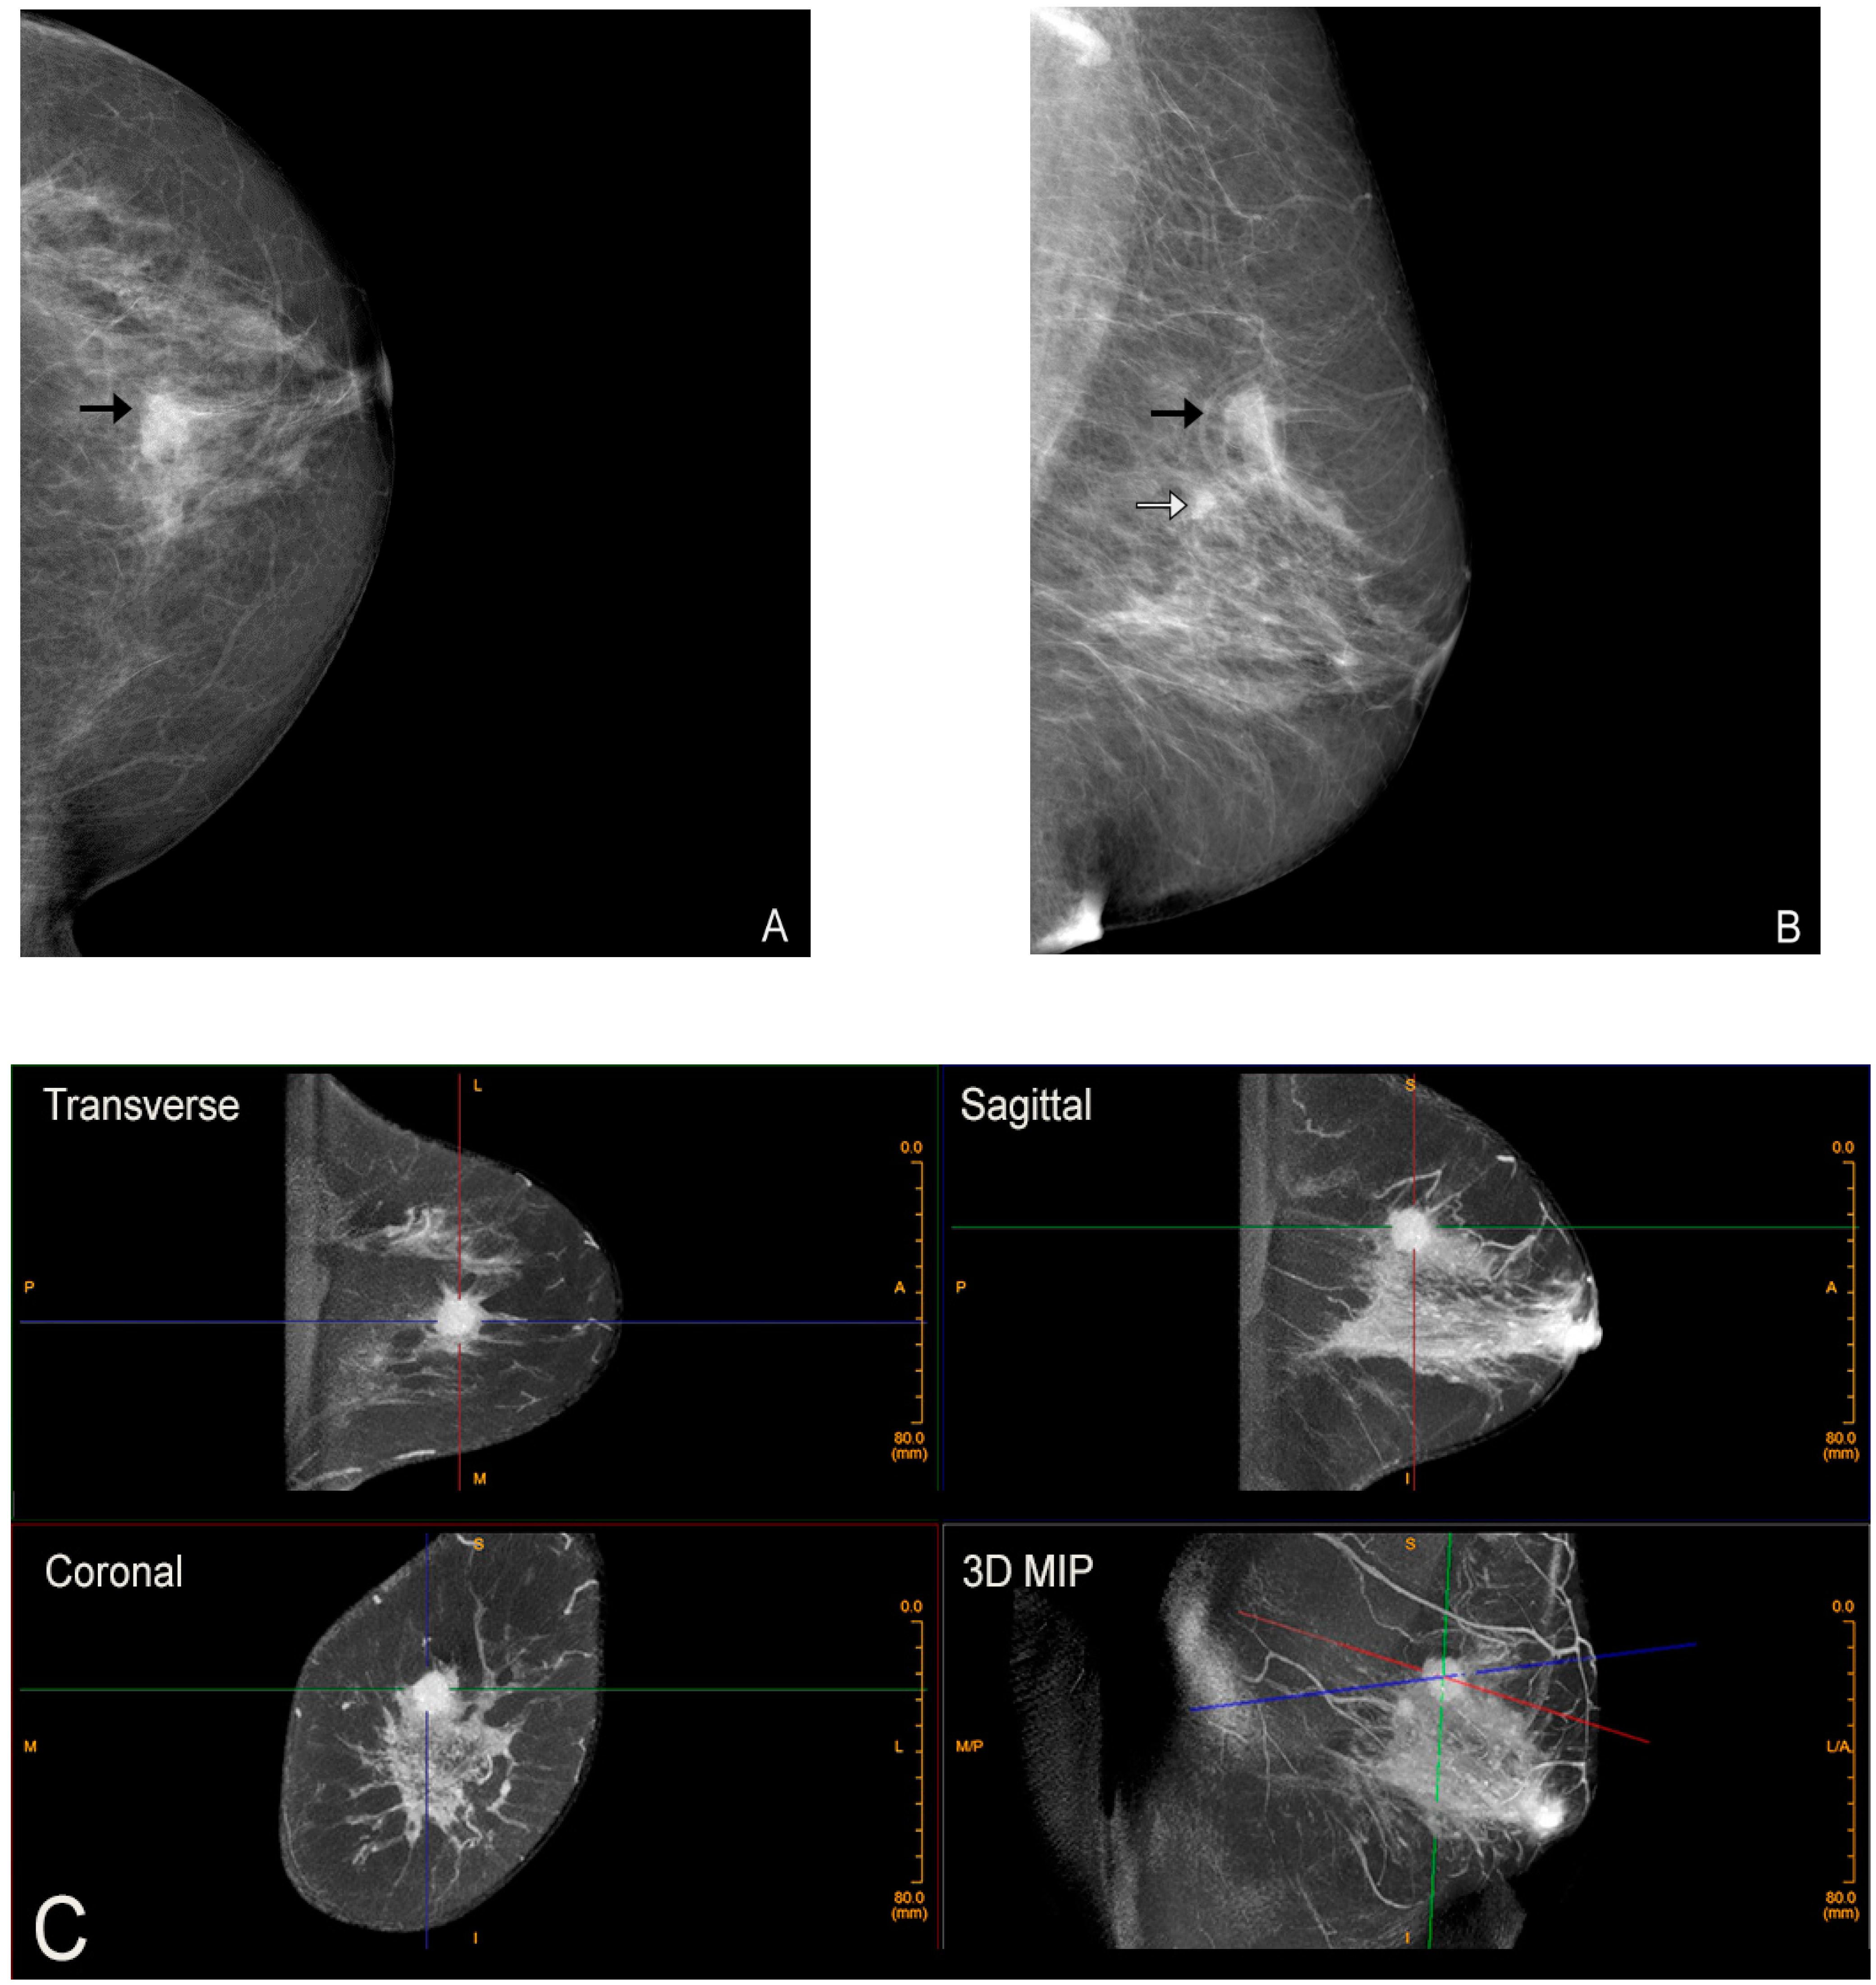

Figure 3.

Advantage of CBBCT over mammography for imaging dense breast tissue. Bilateral CC (A) and bilateral MLO (B) views demonstrate dense breasts without focal findings consistent with a negative or BI-RADS 1 mammogram. (C) Post-contrast CBBCT demonstrates a mass denoted by guidelines that is easily recognized consistent with cancer.